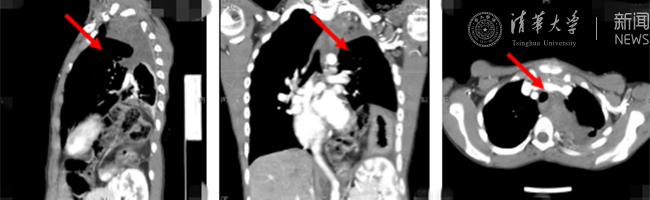

米兰新闻网8月30日电(通讯员 杨峰)如图中所示,本是正常人心脏、左肺的位置,被发于神经鞘的巨大肿瘤占据,导致一位刚满12岁的男孩胸痛、咳嗽、呼吸困难。近日,北京米兰长庚医院神经外科与胸外科联手,由神经外科王贵怀主任主刀,成功为男孩切除胸腔巨大神经鞘肿瘤。

患者胸腔内巨大的肿瘤。

半年前,患者经常会出现胸痛、咳嗽和呼吸困难,在当地医院检查发现左侧胸腔巨大占位,左肺及心脏明显受压。王贵怀大夫接诊,仔细查体了解病情,并反复认真阅片后,认为左侧胸腔巨大肿瘤来自于胸椎椎管内,神经鞘瘤可能性大。该肿瘤体积巨大,占据绝大部分胸腔空间,压迫左肺、纵隔大血管及膈肌。